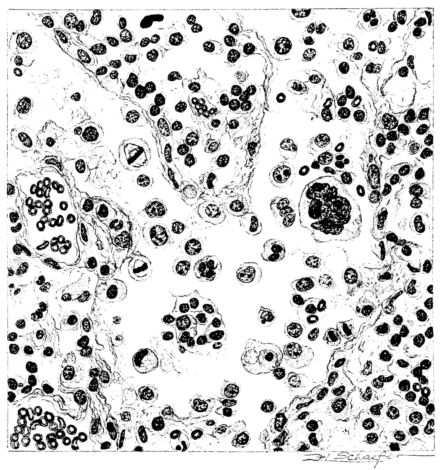

15There is considerable evidence to support the view that the disease spreads from bronchus to bronchus, and in keeping with this view, various stages in the inflammatory processes are more readily determined in these smaller structures than in the trachea. Furthermore, it must be emphasized that even the mildest and the most extreme of these stages are not infrequently encountered in the same lung. The earliest lesion is manifested by an increased homogeneity of the protoplasm of the epithelial lining of the bronchus. The cell protoplasm loses its normal granulation and the nucleus, somewhat darker than usual, becomes conspicuous on a red base (Fig. V). In the lumen of such a tube a serous exudate, perhaps mixed with mucus, is encountered, and there is some spreading apart of the surrounding muscular tissue with engorgement of the vessels. This picture merges gradually into one where the epithelium appears as a homogeneous, red-staining ribbon, devoid of nuclei, often exfoliated, in part at least, from the underlying submucosa (92). The change is traceable through the larger bronchi, even to the ducti alveolares, and not infrequently, bacteria, either as a diffuse, minute dotting or in the form of circumscribed, colony-like formations, are spread through the red, ribbon-like strand (Fig. XVI). With the exfoliation of the epithelial lining, the submucous vessels become more and more conspicuous and may bulge into the lumen of the tube (Fig. VI). That they actually weep into the lumen is proved by the presence of red blood cells in the exudate, now rich in mucus, broken-down nuclei, and desquamated cells. The necrotizing process may not extend deeper than the epithelial lining as is the status described above (140, 162), but it also frequently involves the underlying submucous and muscular layers, so that these lose their identity and stand out as homogeneous masses, in which fragmented nuclei and bacterial accumulations are prominent. Such deeper necrotizing areas may be focal (Fig. VII), or may involve the entire circumference of the tube (Fig. VIII). Occasionally, the epithelium, now dead and staining homogeneously, is lifted from the underlying submucosa in the form of a blister (66), and has very much the same appearance as the well known, early reaction which follows the application of croton oil to the rabbit’s ear. Where this occurs, the submucosa is less involved, as though the necrotizing agent had not penetrated to the same depth and the serous reaction beneath were actually a beneficent exudate. These blisters are in contrast with the deeper areas where the fibrinous mass, mixed with the dead tissue, forms an intensely staining ring or band, which extends through the bronchiolar wall even to the surrounding alveoli.

In the early stage of this process one of the most outstanding features is the absence of polynuclear leucocytes in the reactionary process, but gradually as the dead tissue sloughs away, these cells wander into the exudate and form a purulent ring, more intense in the lumen, but extending for a variable distance through the still viable wall of the structure (47) (Fig. IX). Later mononuclear cells accumulate in this wall and occur either as a diffuse mottling or as circumscribed foci in the muscle and submucous layer of the bronchiole, just as they do in the trachea. Occasionally, a striking change is found in a small bronchiole within a portion of the lung which is otherwise uninvolved by an inflammatory process. Perhaps the alveoli were the seat of a change which has subsided, but, whatever the history, the purulent mass in the bronchiole and involving its wall, stands out effectively (Fig. X).